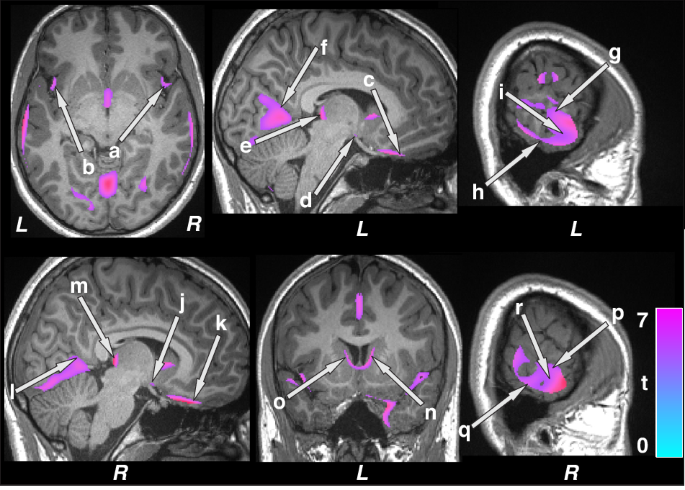

Brain regions with reduced gray matter volumes were observed in the bilateral insula (a, b), ventral medial prefrontal cortices (c, k), hypothalamus (d, j), posterior thalamus (e, m), lingual gyrus (f, l), inferior (h, q), mid (i, r), and superior (g, p) temporal cortices, and caudate (n, o) in patients with epilepsy over controls. Figure conventions are the same as in Fig. 1.

Regional gray matter volume changes

Multiple brain areas showed increased regional gray matter volume in children with epilepsy compared to control subjects (Fig. 1; covariates, age, sex, and BMI), including the bilateral cerebellar cortex (a, b), hippocampus (c, g), amygdala (d, e), putamen (f, h), mid (i), and posterior (m) cingulate, right thalamus (j), bilateral para-hippocampal gyrus (k, l), and parietal cortices (n, o). Decreased volumes were prominent in more-rostral regions that serve prominent roles in CO2 and O2 integration, including the posterior thalamus (Fig. 2 e, m), and blood pressure regulation, including the bilateral ventral medial frontal cortices (c, k), bilateral insula (a, b) and hypothalamus (d, j). Decreased gray matter volumes also appeared in inferior (h, q), mid (i, r), and superior (g, p) temporal cortices, lingual gyrus (f, l), and caudate (n, o) in pediatric patients with epilepsy compared to controls (Fig. 2). Similar regions emerged showing increased gray matter volumes in children with epilepsy compared to controls after controlling for additional covariates including symptomatic epilepsy, nocturnal seizures, and neurodevelopmental disabilities (Supplementary Fig. 1). However, fewer sites with decreased gray matter volumes appeared in children with epilepsy compared to healthy controls after accounting for additional covariates (Supplementary Fig. 2).